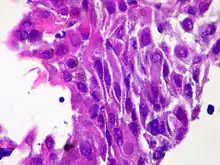

| Micrograph of squamous-cell carcinoma (H&E stain) | |

Squamous epithelial cells are not found in a normal thyroid, so the origin of SCT is not clear. However, it might be derived from embryonic remnants such as thyroglossal ducts or branchial clefts. Often, SCT is diagnosed in one of the thyroid lobes but not in the pyramidal lobe. Another possible way of developing SCT is through the squamous metaplasia of cells. However, that theory is also controversial since Hashimoto's thyroiditis and chronic lymphocytic thyroiditis (neoplasms to be shown squamous metaplasia) are not associated with SCT. Primary STC is usually diagnosed in both lobes of the thyroid gland. The histopathology of STC shows a squamous differentiation of tumor cells.